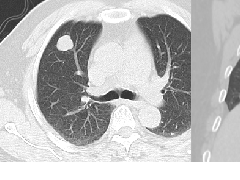

下图是以GGO为主导模式的病人。

此外,还有牵张性支气管扩张,表明存在纤维化。

本例为非特异性间质性肺炎(NSIP)的可能模式之一。

NSIP组织学特征是与不同程度的纤维化相关的细胞间质炎症的相对统一的模式。

与通常的间质性肺炎(UIP)一样,它主要累及下叶的依赖区,但NSIP缺乏蜂窝状的广泛纤维化。

NSIP可能是特发性疾病或与胶原血管疾病或接触药物或化学品有关。

NSIP的预后相对较好,大多数患者对糖皮质激素治疗有反应。

这一结果与UIP的结果有很大的不同,UIP的预后很差。